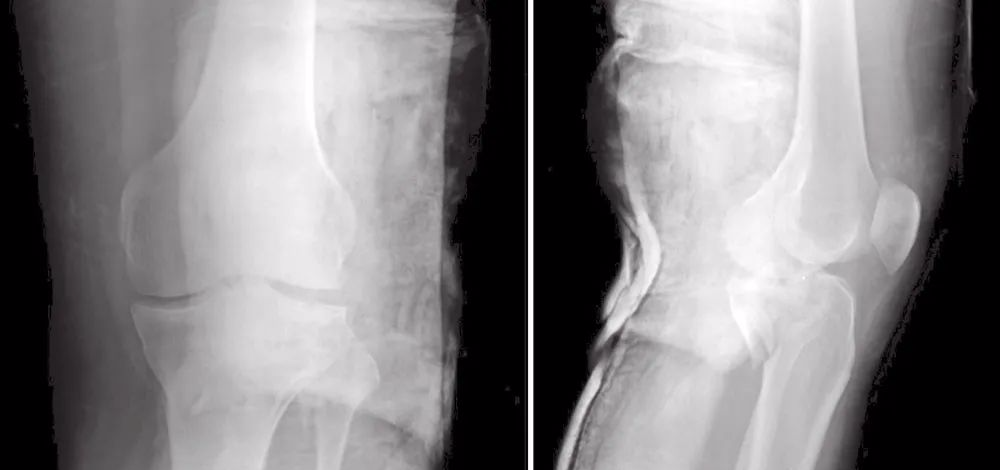

图17 术前X线片

图18 术前CT扫描

图19 A和B冠状位CT图像显示后部的粉碎(A),前柱完整(B)

图20 A和B矢状位显示冠状的骨折线位于中间(A)和外侧(B)

图21 术后X线片

图22 术后1年随访的X线片

图23 显示临床功能

27岁男性患者,在交通意外中受伤。他从自行车上跌落,诉左膝严重疼痛,伤后无法站立。这是个单独的损伤。X线片(图17)和CT(图18~图20)显示左胫骨平台双髁骨折。用两块内固定钢板进行开放复位和内固定(图21)。患者术后1年,影像学表现良好(图22),临床功能(图23)恢复良好。